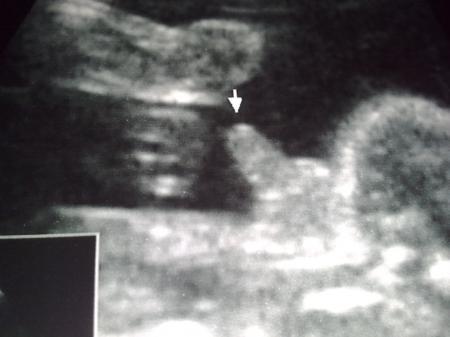

Bild zu